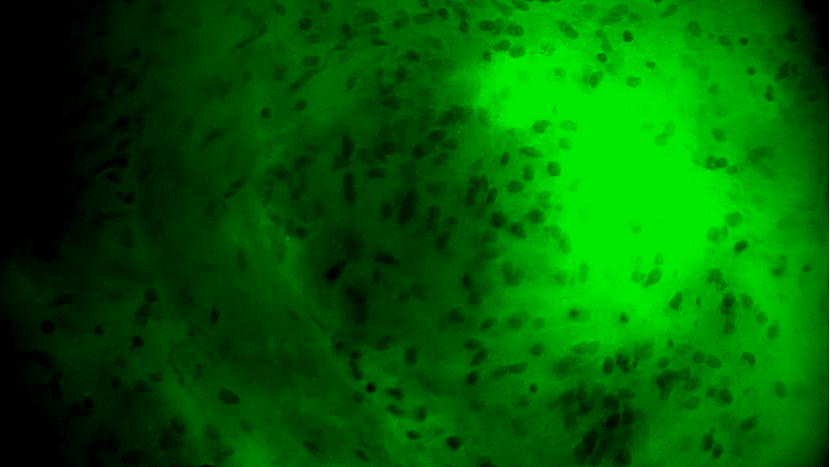

術(shù)中EndoSCell?細(xì)胞圖像如下:

腫瘤中心區(qū)域:細(xì)胞核異型性顯著,分布密集且不規(guī)則,陽性。